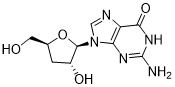

馬鞍山致研生物醫(yī)藥科技有限公司成立于馬鞍山市鄭浦港新區(qū)現(xiàn)代產(chǎn)業(yè)園。公司專(zhuān)注于生物小分子、醫(yī)藥中間體相關(guān)產(chǎn)品的研發(fā)和生產(chǎn),產(chǎn)品主要包括DNA亞磷酰胺單體、RNA亞磷酰胺單體、特殊單體以及按照客戶(hù)要求定制的RNA和DNA,并且公司提供定制合成等方面的研究服...

馬鞍山致研生物醫(yī)藥科技有限公司成立于馬鞍山市鄭浦港新區(qū)現(xiàn)代產(chǎn)業(yè)園。公司專(zhuān)注于生物小分子、醫(yī)藥中間體相關(guān)產(chǎn)品的研發(fā)和生產(chǎn),產(chǎn)品主要包括DNA亞磷酰胺單體、RNA亞磷酰胺單體、特殊單體以及按照客戶(hù)要求定制的RNA和DNA,并且公司提供定制合成等方面的研究服...